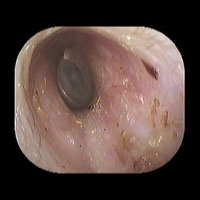

湿性耳垢による耳垢栓塞

耳垢が隙間なく詰まっています。やや聞こえが悪くなります。耳鼻科用ピンセットで摘出しました。